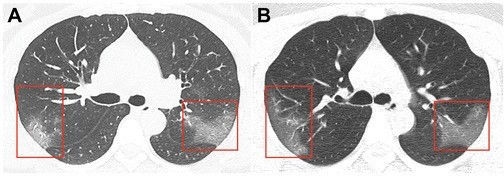

News24.az xəbər verir ki, dərc edilmiş şəkillər Çinin Lançjou şəhərində 39 dərəcə temperaturla xəstəxanaya yerləşdirilmiş 33 yaşlı qadının kompüter tomoqrafiyasıdır.

Birinci şəkildə görünən "tutqun şüşə effekti” üç gün sonra çəkilmiş ikinci şəkildə daha da artır.

Bu fotolar tibb aləminə virusu müəyyən etməkdə yardımçı olacaq.